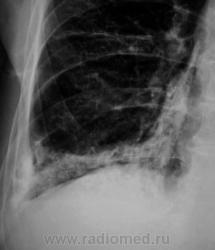

Пациент направлен на рентгенографию ОГК.

А томограмм нет. Просто демонстируется обызвествленная плевра.